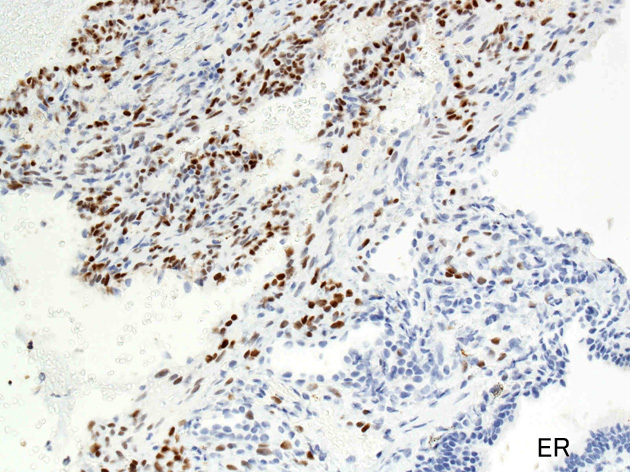

LAMの肺病変

嚢胞周囲または肺血管, リンパ管, 細気管支にそうLAM cellの浸潤, 集簇を特徴とする。LAM cellには2種類が認められ, 小型紡錘形細胞と細胞質の豊富な類上皮様細胞があり, 紡錘型は主に集簇巣の中心に存在し増殖能が高い。 類上皮様LAM cellは辺縁部に多く, 増殖能は低いがHMB45を強く発現している。

LAM cellの免疫染色--SMA, desmin, vimentin(vimentinはいつも陽性とはならない)が陽性となりmuscle lineageであるが典型的な筋細胞と異なり,

嚢胞形成はLAM cellの増殖と関連しており, 細胞が産生するmatrix metalloproteinases(MMPs)による組織破壊によるらしい。

免疫染色